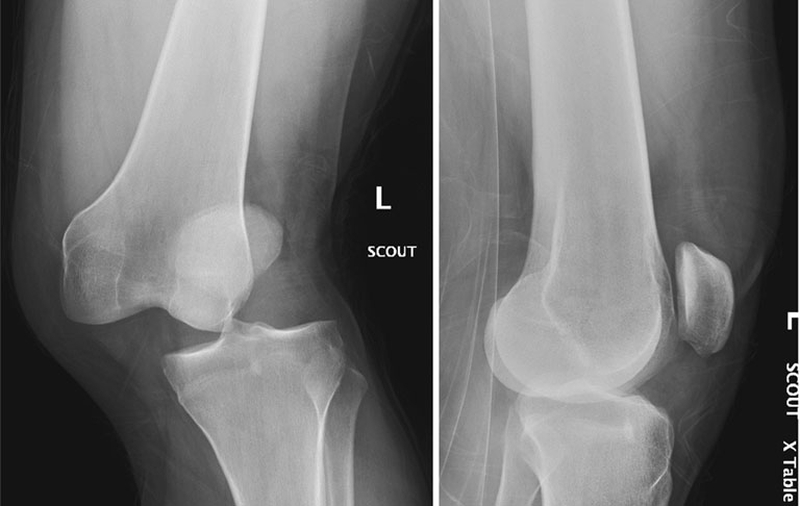

Trật xương bánh chè có thể hiểu đơn giản chính là tình trạng xương bánh chè do chấn thương bị lệch khỏi vị trí ban đầu. Biểu hiện của bệnh nhân không rõ ràng, nhưng có thể nhận ra nhờ tình trạng khó mở, hoặc không thể mở đầu gối.

Trật xương bánh chè thường xảy ra do chấn thương, thường là những chấn thương xoắn không có tiếp xúc trực tiếp với đầu gối hoặc là do một cú đánh trực tiếp vào mặt giữa của đầu gối. Những bệnh nhân bị lỏng dây chằng toàn thân có nguy cơ trật xương bánh chè nhiều hơn. Ngoài ra cũng có xu hướng tái diễn nhiều lần.

Biểu hiện thường gặp nhất của trật xương bánh chè chính là cơn đau đột ngột và tình trạng biến dạng đầu gối sau chấn thương. Người bệnh thường ghi nhận nghe thấy tiếng “bốp” trên gối và sau đó là sưng tấy trong giai đoạn cấp tính. Những triệu chứng dần tồi tệ hơn khi gập gối và quỳ.

Trật xương bánh chè có thể kèm theo tràn dịch khớp hoặc là tổn thương phần mô xung quanh. Ngoài ra còn có lệch xương đùi, lệch xương bánh chè, xoắn xương chày hoặc là lỏng lẻo dây chằng nói chung.

Trên lâm sàng, không khó để xác định và chẩn đoán trật khớp xương bánh chè. Tuy nhiên, việc xác định được chính xác nguyên nhân ở từng trường hợp sai khớp xương bánh chè lại tương đối khó khăn.